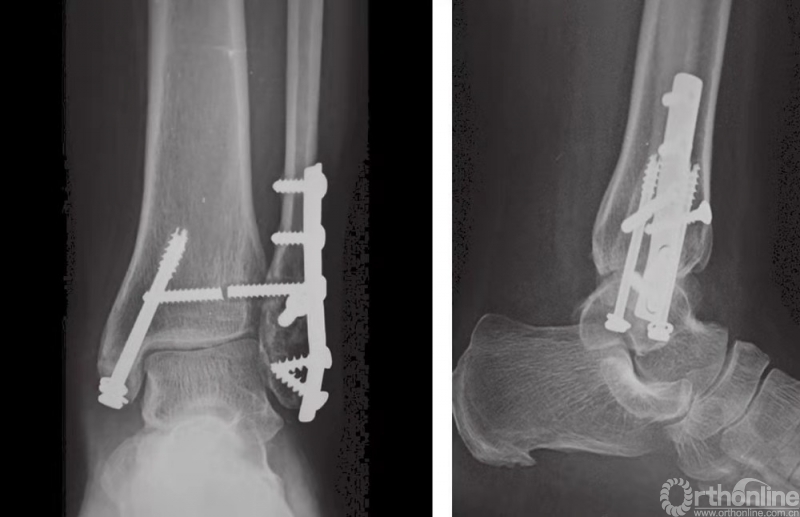

下胫腓联合固定技术

在完成所有踝部骨折的固定之后,应评估下胫腓联合的稳定性。如果下胫腓联合关节上方或下胫腓联合水平发生腓骨骨折,应充分检查下胫腓联合的稳定性。在前后和中外两个平面上,应检查其完整性(图23)。另外,因为下胫腓联合发生损伤时腓骨可能向外旋转,故还应检查腓骨的旋转情况。

图23 用巾钳夹住腓骨向外侧牵拉以评估下胫腓联合的稳定性

如果下胫腓联合不稳,则须进行固定,固定时采用皮质骨螺钉。由于腓骨在解剖关系上位于胫骨的后外侧,因此应将螺钉从后向前以30°的角度嵌入。一般认为,三皮质骨螺钉固定足以保证下胫腓联合的稳定性。螺钉应至少高过关节线2cm(图24和图25)。

图24 下胫腓骨螺钉置入方法

图25 通过钢板的皮质骨螺钉固定旋前外旋型下胫腓联合损伤